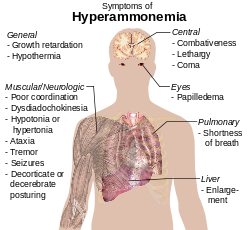

In physiology

Ammonia also plays a role in both normal and abnormal animal physiology. It is biosynthesised through normal amino acid metabolism and is toxic in high concentrations. The liver converts ammonia to urea through a series of reactions known as the urea cycle. Liver dysfunction, such as that seen in cirrhosis, may lead to elevated amounts of ammonia in the blood ( hyperammonemia). Likewise, defects in the enzymes responsible for the urea cycle, such as ornithine transcarbamylase, lead to hyperammonemia. Hyperammonemia contributes to the confusion and coma of hepatic encephalopathy, as well as the neurologic disease common in people with urea cycle defects and organic acidurias.

Ammonia is important for normal animal acid/base balance. After formation of ammonium from glutamine, α-ketoglutarate may be degraded to produce two molecules of bicarbonate, which are then available as buffers for dietary acids. Ammonium is excreted in the urine, resulting in net acid loss. Ammonia may itself diffuse across the renal tubules, combine with a hydrogen ion, and thus allow for further acid excretion.